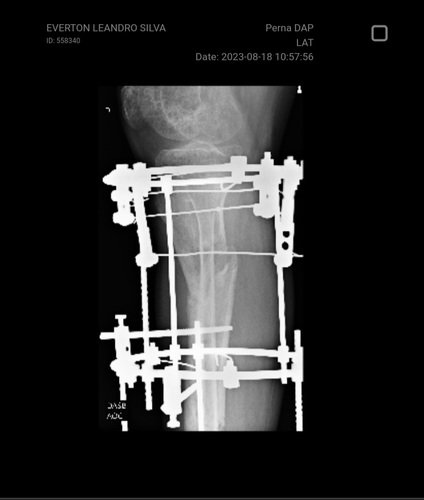

Minha perna como está hoje quase um ano após o acidente.

Meu nome é Everton, tenho 46 anos e dia 24 de Dezembro de 2022 juntamente com meu filho, sofremos um acidente de trânsito.Comecei usando um fixador externo, pois tive uma grave fratura exposto quebrando o osso da tibia, e outros lugares na minha perna direta.Depois disso, pela gravidade, fui transferido ao hospital regional de Caraguatatuba, onde passei por outra cirurgia, tirando o fixador externo e substituindo pelo illizarov (gaiola) para maior fixação dos ossos.Minha 2⁰ cirurgia foi realizada em 7 de Janeiro e desde então tenho ido às consultas de rotina em Caraguatatuba passando pelo mesmo ortopedista que vinha me orientado sobre as possíveis evoluções que eu poderia ter, baseado no raio X que ele via;Nas minhas últimas consultas com ele e sem perspectiva de calcificação dos ossos, esse ortopedista fez eu assinar um termo, no qual eu passaria por outra cirurgia para reconstrução e modificação da estrutura dos ferros em minha perna. Isso foi em Outubro de 2023...Fiz todos os exames que esse ortopedista me pediu, e fui pra casa aguardar eles entrarem em contato, o que não acontecia. Quanto tempo?Durante esse período tive complicações com a minha perna (inchaço, inflamação, infecção, febre, vazamentos de secreções e dores insuportável, etc.)Ligamos no hospital Regional de Caraguatatuba e a resposta foi: não termos vagas!Entrei para a entrada de emergência e ao acionarem o ortopedista, para a minha surpresa, era outro ortopedista e com outro diagnóstico. Tirou o raio X da minha perna e falou o que eu estava passando era normal, ou seja, não é grave. Ali mesmo, pra aliviar a minha dor tirou um dos pinos sem anestesia, pois minha perna estava inchada, cor escura e muita secreção sai pelos ferros.Sobre o que ele viu no raio X:Ele disse que nenhum dos meus ossos estão consolidados (colados), então teria que ser estudado sobre o que fazer. Questionei o Doutor pois eu já estava aguardando uma cirurgia próxima à cirurgia que seria agendada. Sendo este médico um novo a avaliar meu caso.Agora esse novo ortopedista está com outro diagnóstico sobre a minha situação.Disse que meus ossos não colaram e que eu teria que ficar em casa aguardando, me dando medicamentos fortes para tirar a dor o qual não tem passado, e pouco me aliviado.Sobre a cirurgia marcada...Simplesmente anularam e não sabem nada a respeito pois não sabem do pedido do ortopedista que foi transferido.Enfim decidi pedir ajuda para que eu possa procurar uma segunda opinião médica, onde não apenas me mandem pra casa tomando remédios onde nada me ajuda, ajuda em outro hospital, outra cidade e isso me gera custos onde não tenho para os custos.